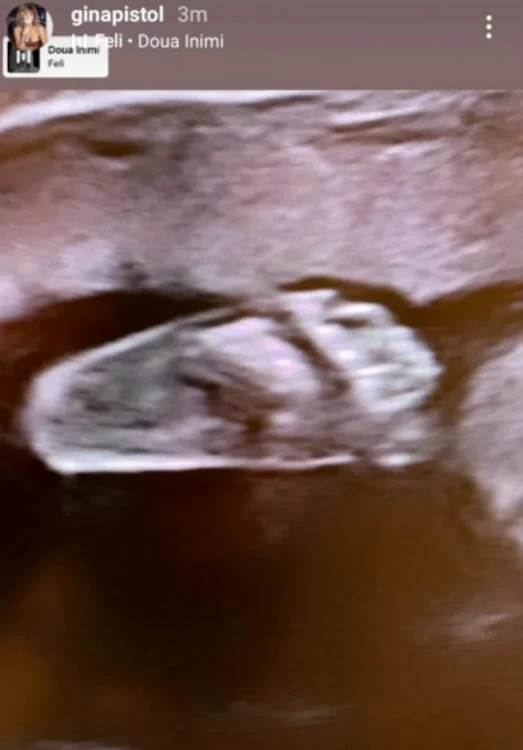

Prezentatoarea emisiunii „Chefi la cuțite” a trecut pe la cabinetul medicului care îi monitorizează sarcina zilele acestea și a făcut o ecografie, pe care a publicat-o pe contul personal de Instagram, spre bucuria admiratorilor ei.

Gina Pistol le-a arătat urmăritorilor ei ecografia bebelușului

Astfel, Gina a făcut publică și prima fotografie cu bebelușul din burtică, ea și Smiley urmând să aibă o fetiță.În dreptul imaginii cu ecografia, vedeta a adăugat și melodia „Două inimi”, cântată de Feli, care este fix despre această perioadă a maternității.

„Am ajuns acasă şi sunt epuizată. A fost o zi lungă, sunt trează de la 6:15. Dar sunt foarte fericită, am făcut morfologia trimestrului 2 şi totul este bine. Totul este în grafic. Mi-a fost tare drag să o văd, dar era foarte agitată. Cred că o să îmi semene”, a spus Gina pe rețelele sociale. Gina Pistol s-a întors pe platoul de filmare Chefi la cuțite Emisiunea „Chefi la cuțite” a dat startul filmărilor pentru un nou sezon, sezonul cu numărul 9.